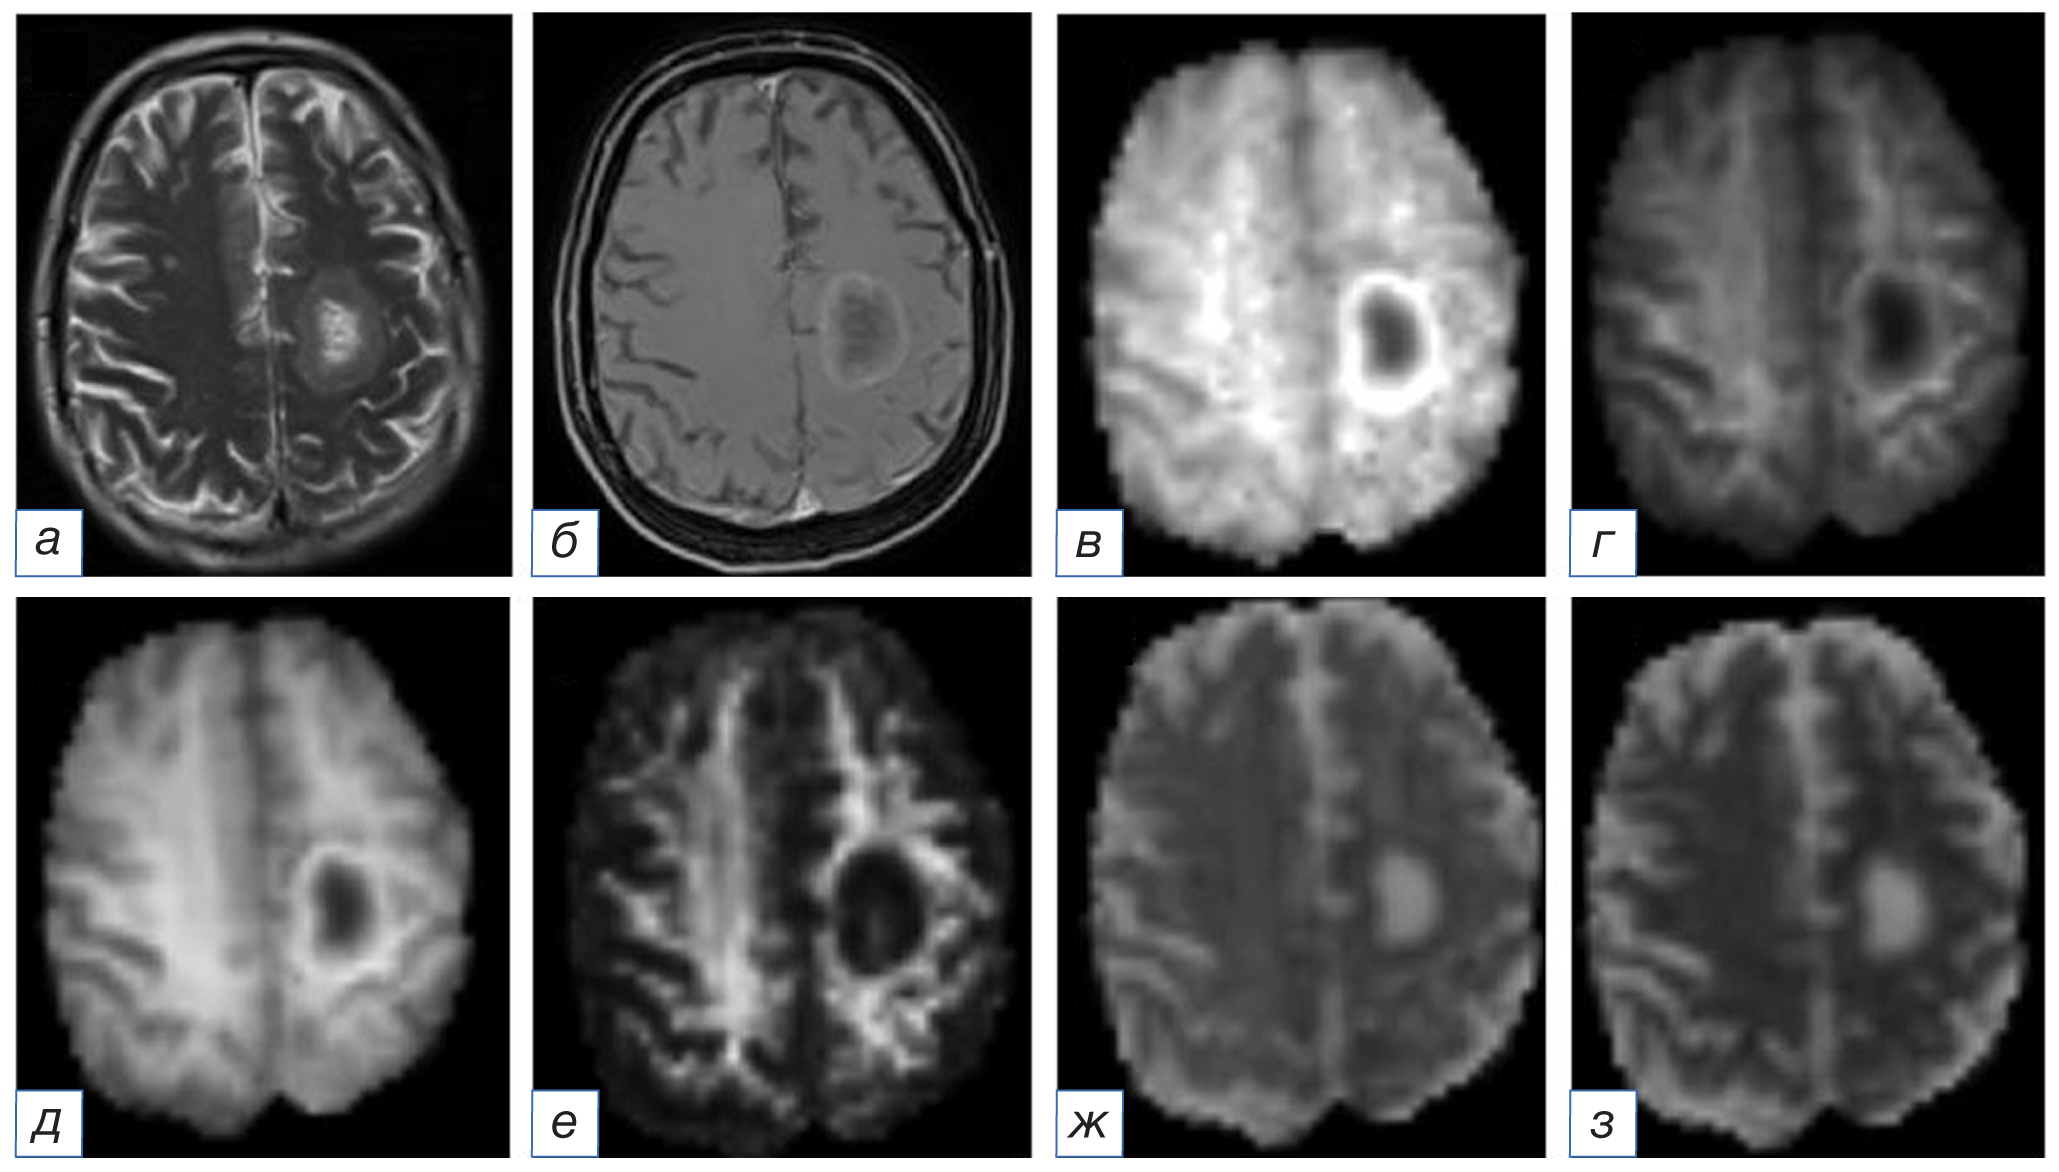

Рис. 4. Магнитно-резонансная томограмма головного мозга: метастаз рака молочной железы в левой лобной доле: а (T2-WI) — в левой лобной доле определяется образование с центральной полостью некроза, окружённое выраженной зоной перифокального отёка; б (Т1-WI после внутривенного введения контрастного вещества) — визуализируется интенсивное неравномерное накопление контрастного препарата, преимущественно по контуру образования; в (аксиальный куртозис) — в левой лобной доле образование определяется в виде участка гетерогенного МР-сигнала, гипоинтенсивного в центральных отделах; г (радиальный куртозис) — в левой лобной доле образование определяется в виде участка гетерогенного МР-сигнала, гипоинтенсивного в центральных отделах, слабого гиперинтенсивного по периферии; д (средний куртозис) — в левой лобной доле образование определяется в виде участка гетерогенного МР-сигнала, гипоинтенсивного в центральных отделах; е (куртозисная анизотропия) — в левой лобной доле образование определяется в виде участка преимущественно пониженного МР-сигнала; ж (аксиальная диффузия экстрааксональной жидкости) — в левой лобной доле образование определяется в виде участка гетерогенного МР-сигнала, гиперинтенсивного в центральных отделах и слабого гипоинтенсивного по периферии; з (радиальная диффузия экстрааксональной жидкости) — в левой лобной доле образование определяется в виде участка гетерогенного МР-сигнала, гиперинтенсивного в центральных отделах и гипоинтенсивного по периферии.